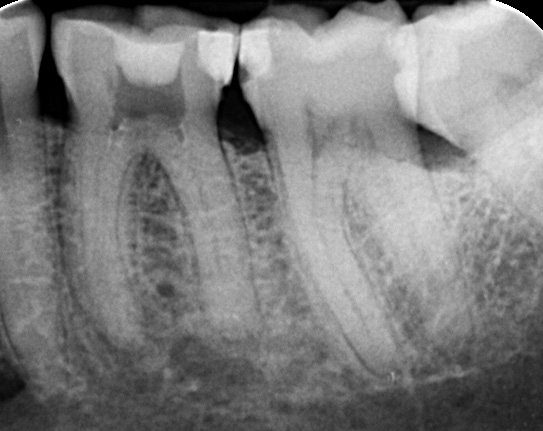

You may need root canal treatment if the pulp becomes inflamed or dies due to significant decay, a large restoration (filling or crown), or trauma. When the pulp dies, the tooth root system rapidly becomes infected with bacteria, resulting in an infected pulp.

Signs include an inflamed pulp that may cause a toothache, or a dead pulp where the root canal becomes rapidly infected with bacteria. This infection may cause pain and swelling in the supporting tissues (an abscess) or the tooth may remain symptom-free. The need for treatment is often caused by significant decay, a large restoration (filling or crown), or trauma to the tooth.